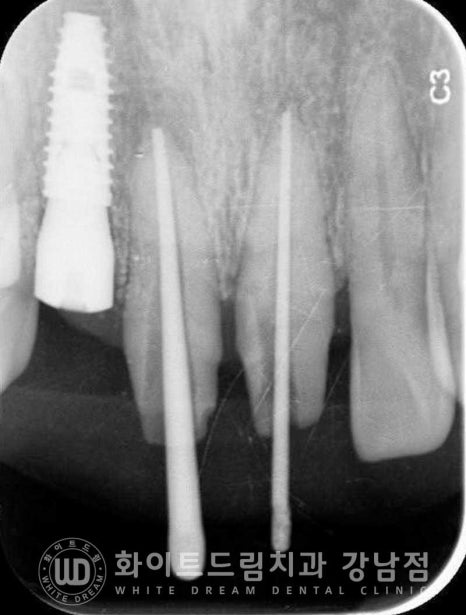

우선 흔들리는 치아를 발치한 후 바로 임플란트를 식립했고 염증으로 녹은 잇몸뼈는

추가적인 뼈이식을 통해 보강하여 치료를 진행하게 되었습니다.

12번 임플란트가 골 유착되는 회복 기간 동안에는 남은 11, 21번 치아의 신경치료와

잇몸치료를 동반하게 되었습니다.

치료가 마무리되기 전까지는 임시치아를 세팅해 드려